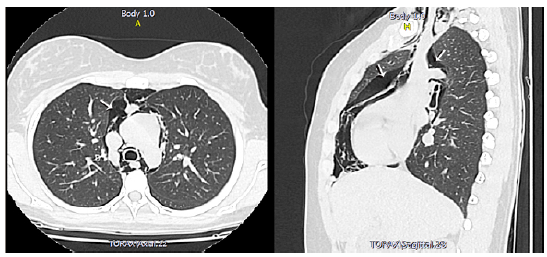

Posteroanterior and lateral chest x-rays were taken, showing normal cardiac silhouette without pleural effusions or flattening of the diaphragm, but increased bronchovascular network without consolidation towards the lung bases and subcutaneous emphysema towards the right supraclavicular region with posible pneumomediastinum (Figure 1).

Posteroanterior and lateral chest x-rays. => Subcutaneous emphysema in right supraclavicular region and air in mediastinum.

Figure 1: Posteroanterior and lateral chest x-rays. => Subcutaneous emphysema in right supraclavicular region and air in mediastinum.

Source: Document obtained during the study.